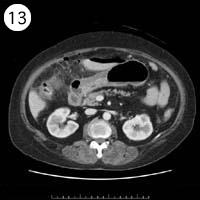

57歳 女性

単純CT

造影CT